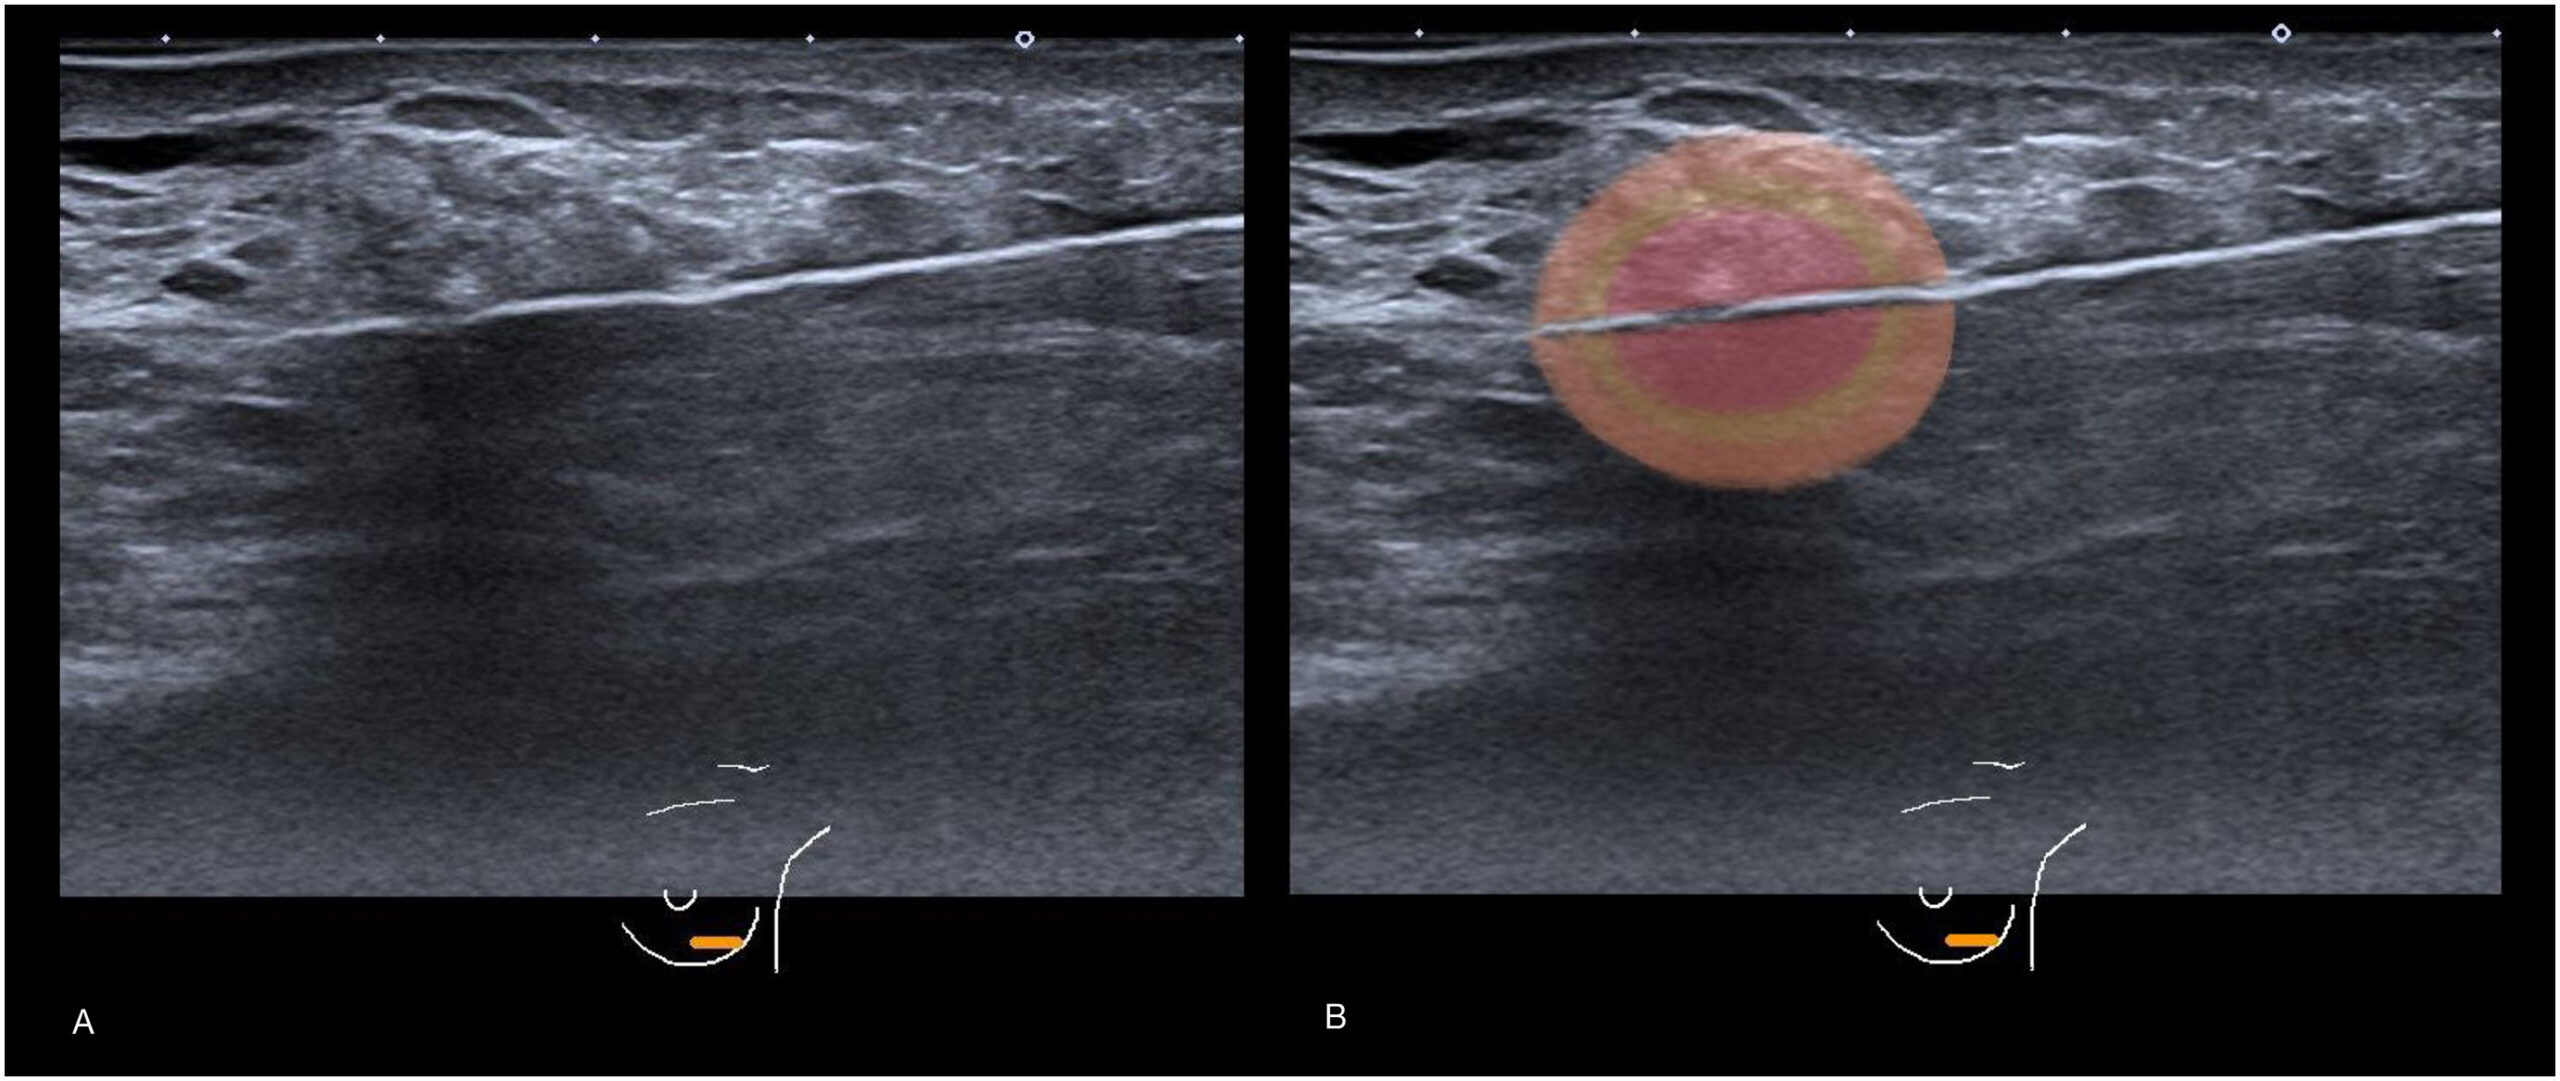

Registro con microelectrodos

Los microelectrodos tienen una punta muy fina, lo suficientemente pequeña para poder registrar la actividad eléctrica de neuronas individuales. Por lo general esta técnica se denomina registro de neuronas individuales o de unidades. Los electrodos se implantan en el encéfalo de los animales mediante cirugía estereotáxica, luego se conectan a unos zócalos de conexión eléctrica y se fijan al cráneo con una pasta especial. Cuando el animal se ha recuperado de la cirugía ya se le puede conectar al sistema de registro. Las señales eléctricas que detectan los microelectrodos son bastante débiles y tienen que amplificarse. Los amplificadores usados convierten las débiles señales registradas en el encéfalo en otras más fuertes, pudiendo ser almacenadas en un ordenador para posteriores análisis.